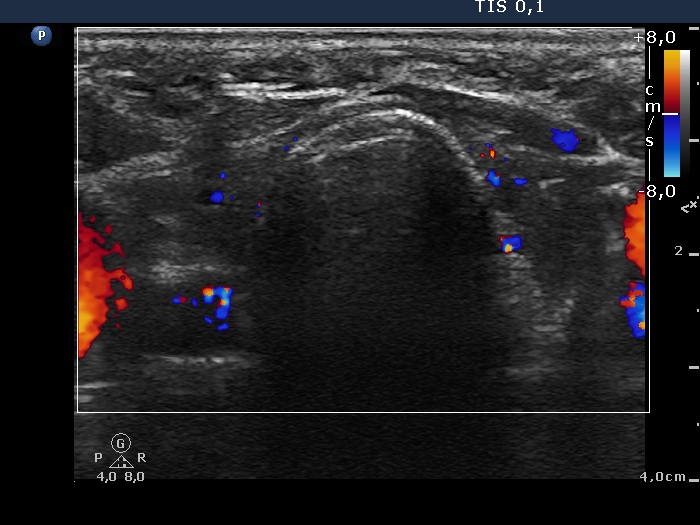

Graves' disease - case 18

Follow-up investigation 6 months after the initial one (ultrasonographic picture 3)

Both lobes, transverse scan, color Doppler method. The vascularization is decreased.